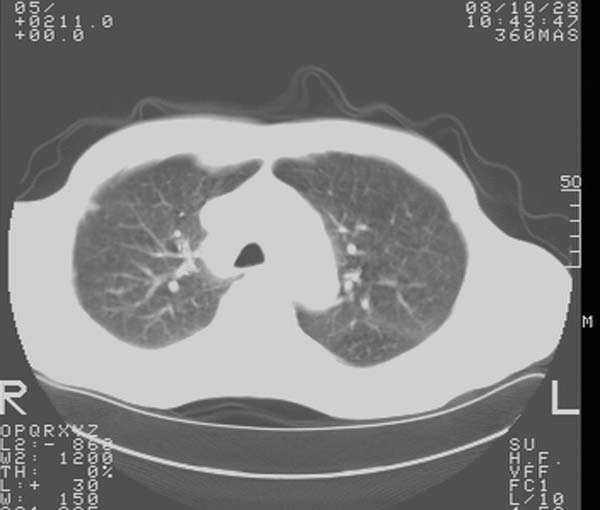

m,65y。半年前发现颈小结节,逐渐增多增大,现双侧耳后、颌下及颈部表浅淋巴肿大。胸片示双肺门增大。外院曾穿刺诊断为淋巴结核。在我科作胸腹部ct,我们觉得外院病检有误。现将图像上传请战友讨论。

纵隔内及腹膜后广泛淋巴结肿大,脾大,肝内似可见低密度影,结合病史半年前发现颈小结节,逐渐增多增大,现双侧耳后、颌下及颈部表浅淋巴肿大。考虑淋巴瘤。

纵隔,双肺门腹膜后多发淋巴结重大,非融合,肝脾轻度肿大,双肺野弥漫性小结节;考虑淋巴瘤,结节病可能性

纵隔内,双肺门、腋窝及腹膜后多发肿大淋巴结影,肺内小结节影,肝脾体积增大,支持淋巴瘤。肝内多发低密度影,考虑小囊肿。

考虑淋巴瘤肺、肝内转移,脾脏肿大。